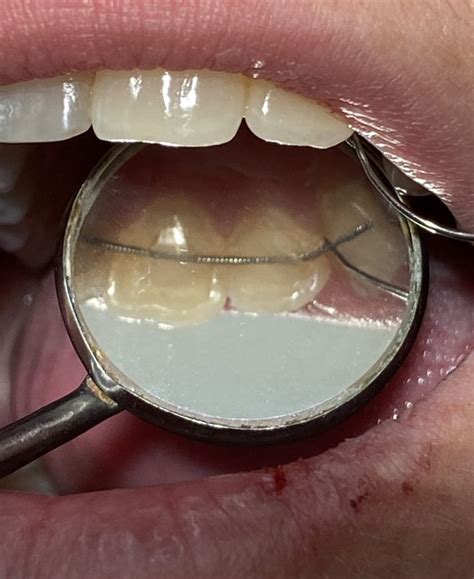

Los retenedores de fibra de vidrio son un tipo de retenedor fijo utilizado en ortodoncia para mantener los dientes en su posición correcta después de retirar los brackets. Están fabricados con fibras de vidrio unidas con resina compuesta, lo que les confiere resistencia y flexibilidad.

Estos retenedores se adhieren a la superficie lingual (interna) de los dientes anteriores, usualmente de canino a canino, para evitar que se muevan y asegurar la estabilidad de la sonrisa a largo plazo.

- Estética: Son prácticamente invisibles, ya que se colocan en la cara interna de los dientes.